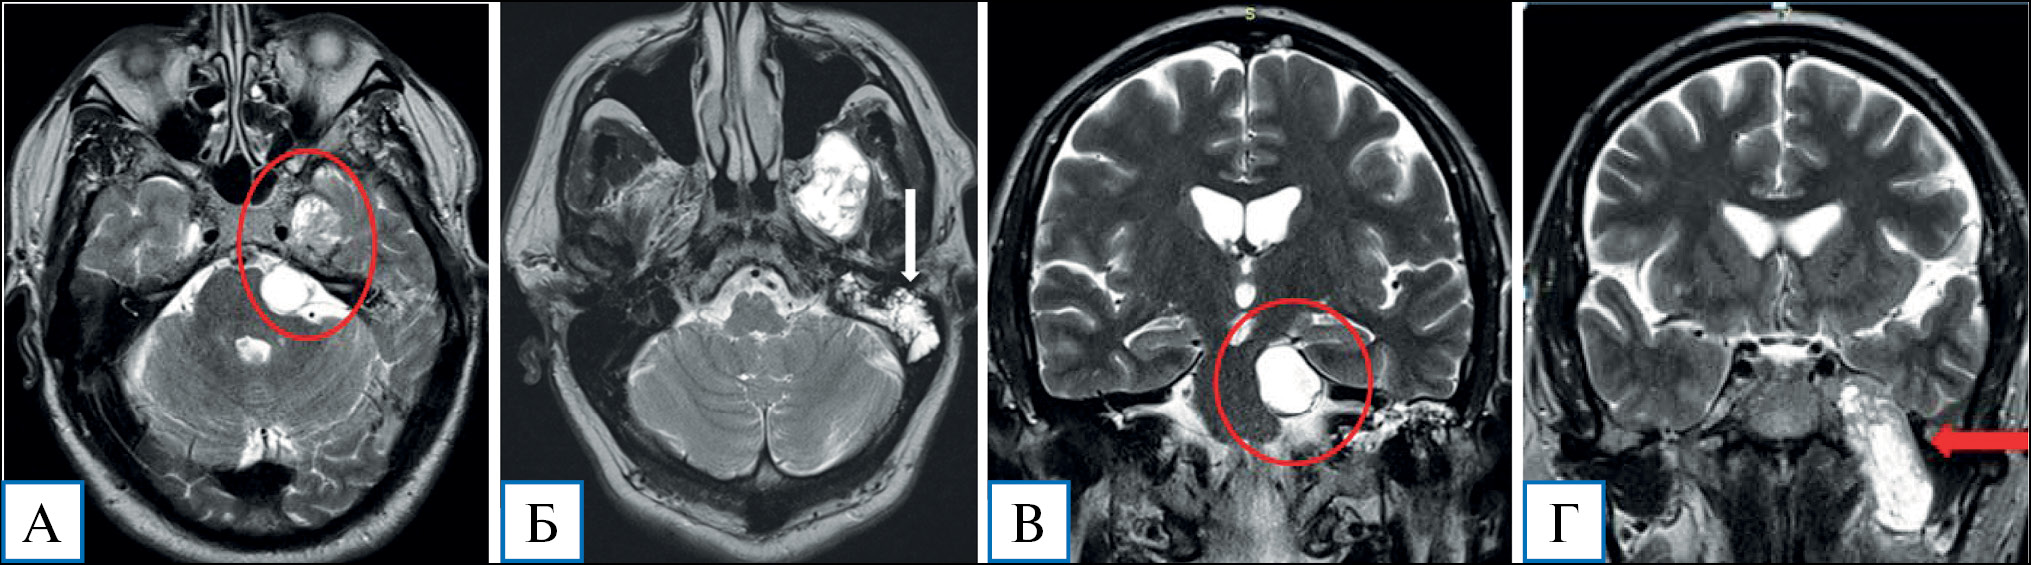

Невринома вызывает компрессию ножек мозга, моста, корешков VII и VIII нервов, а также деструкцию височной кости с развитием петрозита и мастоидита (рис. 2).

Рис. 2. Пациент М. с невриномой тройничного нерва, 60 лет: компьютерная томография головного мозга с контрастным усилением

Примечание. На КТ-изображениях в костном режиме определяются деструкция пирамиды височной кости в проекции меккелевой полости, рваного отверстия (А), а также деструкция основания средней черепной ямки с расширением овального и круглого отверстия (Б).

В первые сутки после операции выполнена КТ головного мозга: опухоль удалена тотально, минимальные послеоперационные ишемические изменения в левой височной доле (рис. 6).

Рис. 6. Пациент М. с невриномой тройничного нерва, 60 лет: компьютерная томография головного мозга с контрастным усилением после операции

Примечание. А — 3D-изображение: определяется лобно-теменно-височный костный лоскут, фиксированный краниофиксами; Б, В — послеоперационные изменения в области основания средней черепной ямки (обозначены овалом); Г — послеоперационные изменения в проекции меккелевой полости (обозначены овалом).